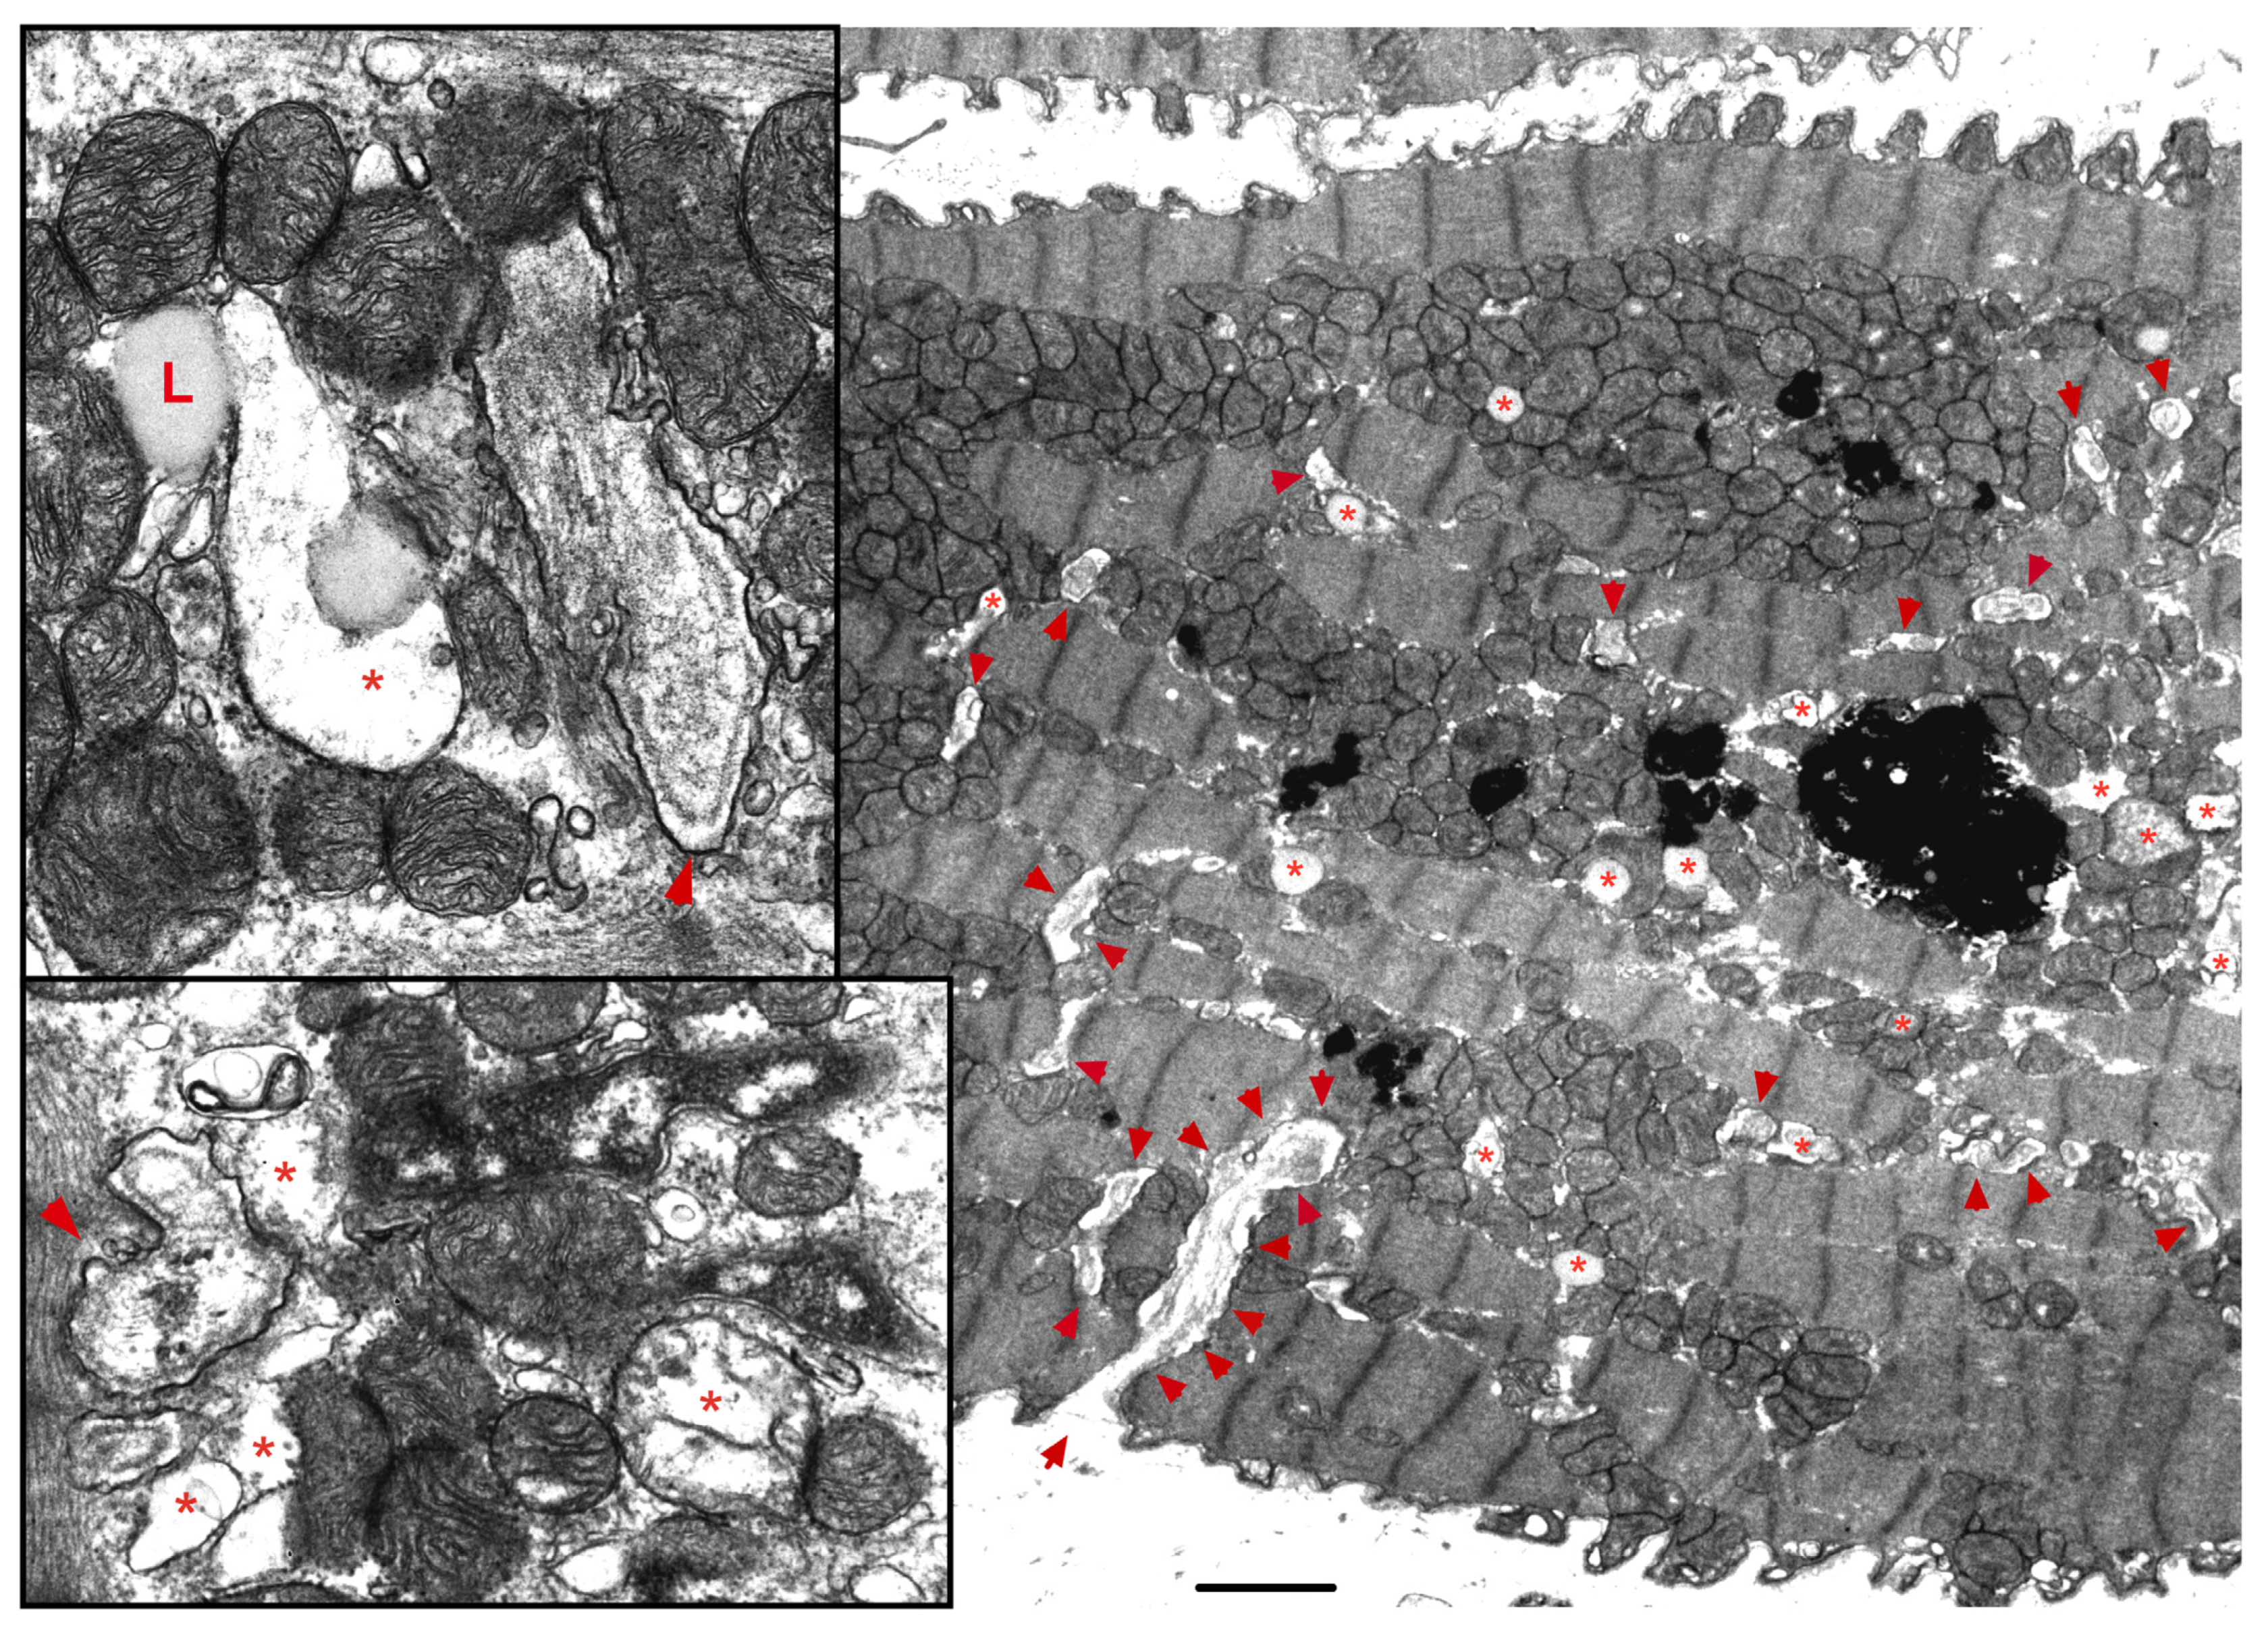

- Chaanine, A.H. Morphological Stages of Mitochondrial Vacuolar Degeneration in Phenylephrine-Stressed Cardiac Myocytes and in Animal Models and Human Heart Failure. Medicina 2019, 55, 239. [Google Scholar] [CrossRef]

- Chaanine, A.H.; Joyce, L.D.; Stulak, J.M.; Maltais, S.; Joyce, D.L.; Dearani, J.A.; Klaus, K.; Nair, K.S.; Hajjar, R.J.; Redfield, M.M. Mitochondrial Morphology, Dynamics, and Function in Human Pressure Overload or Ischemic Heart Disease with Preserved or Reduced Ejection Fraction. Circ. Heart Fail. 2019, 12, e005131. [Google Scholar] [CrossRef]